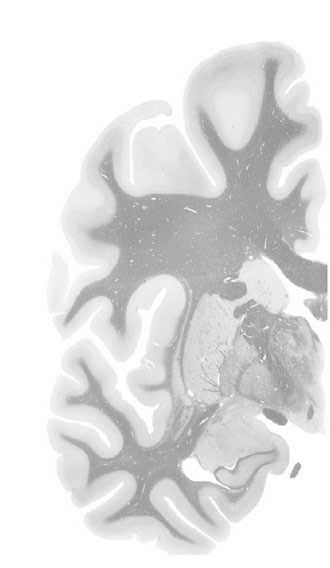

Hi-Resolution Sections · Cells (Nissl Staining) · Virtual Microscopy

Frontal sections (Nissl) from the Atlas Brain:

Slice ID:

r3-1195

Plate NR:

ca 26

Position:

5,5 mm